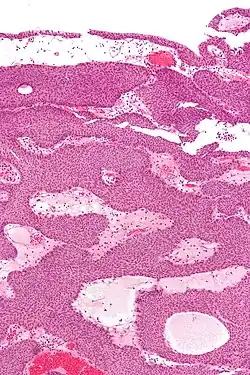

Additional image

An inverted papilloma, also known as Ringertz tumor,[1] is a type of tumor in which surface epithelial cells grow downward into the underlying supportive tissue. It may occur in the nose and/or sinuses or in the urinary tract (bladder, renal pelvis, ureter, urethra). When it occurs in the nose or sinuses, it may cause symptoms similar to those caused by sinusitis, such as nasal congestion. When it occurs in the urinary tract, it may cause blood in the urine.